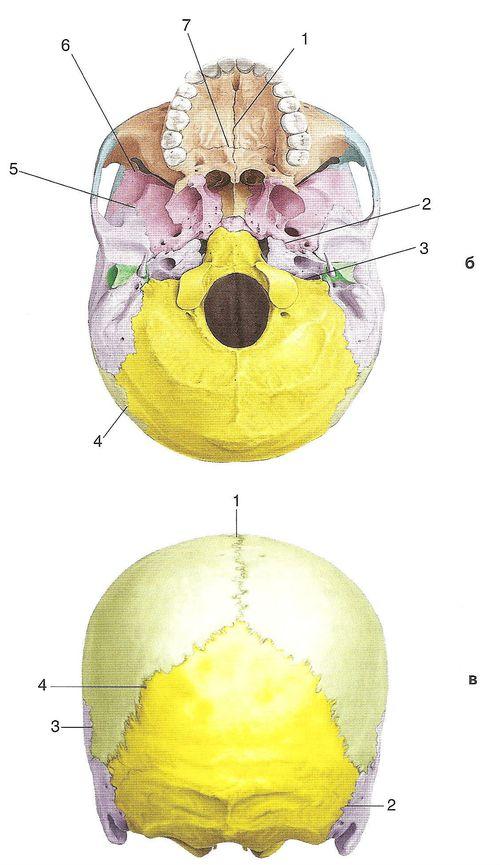

Структура и анатомия синдесмоза: научные иллюстрации